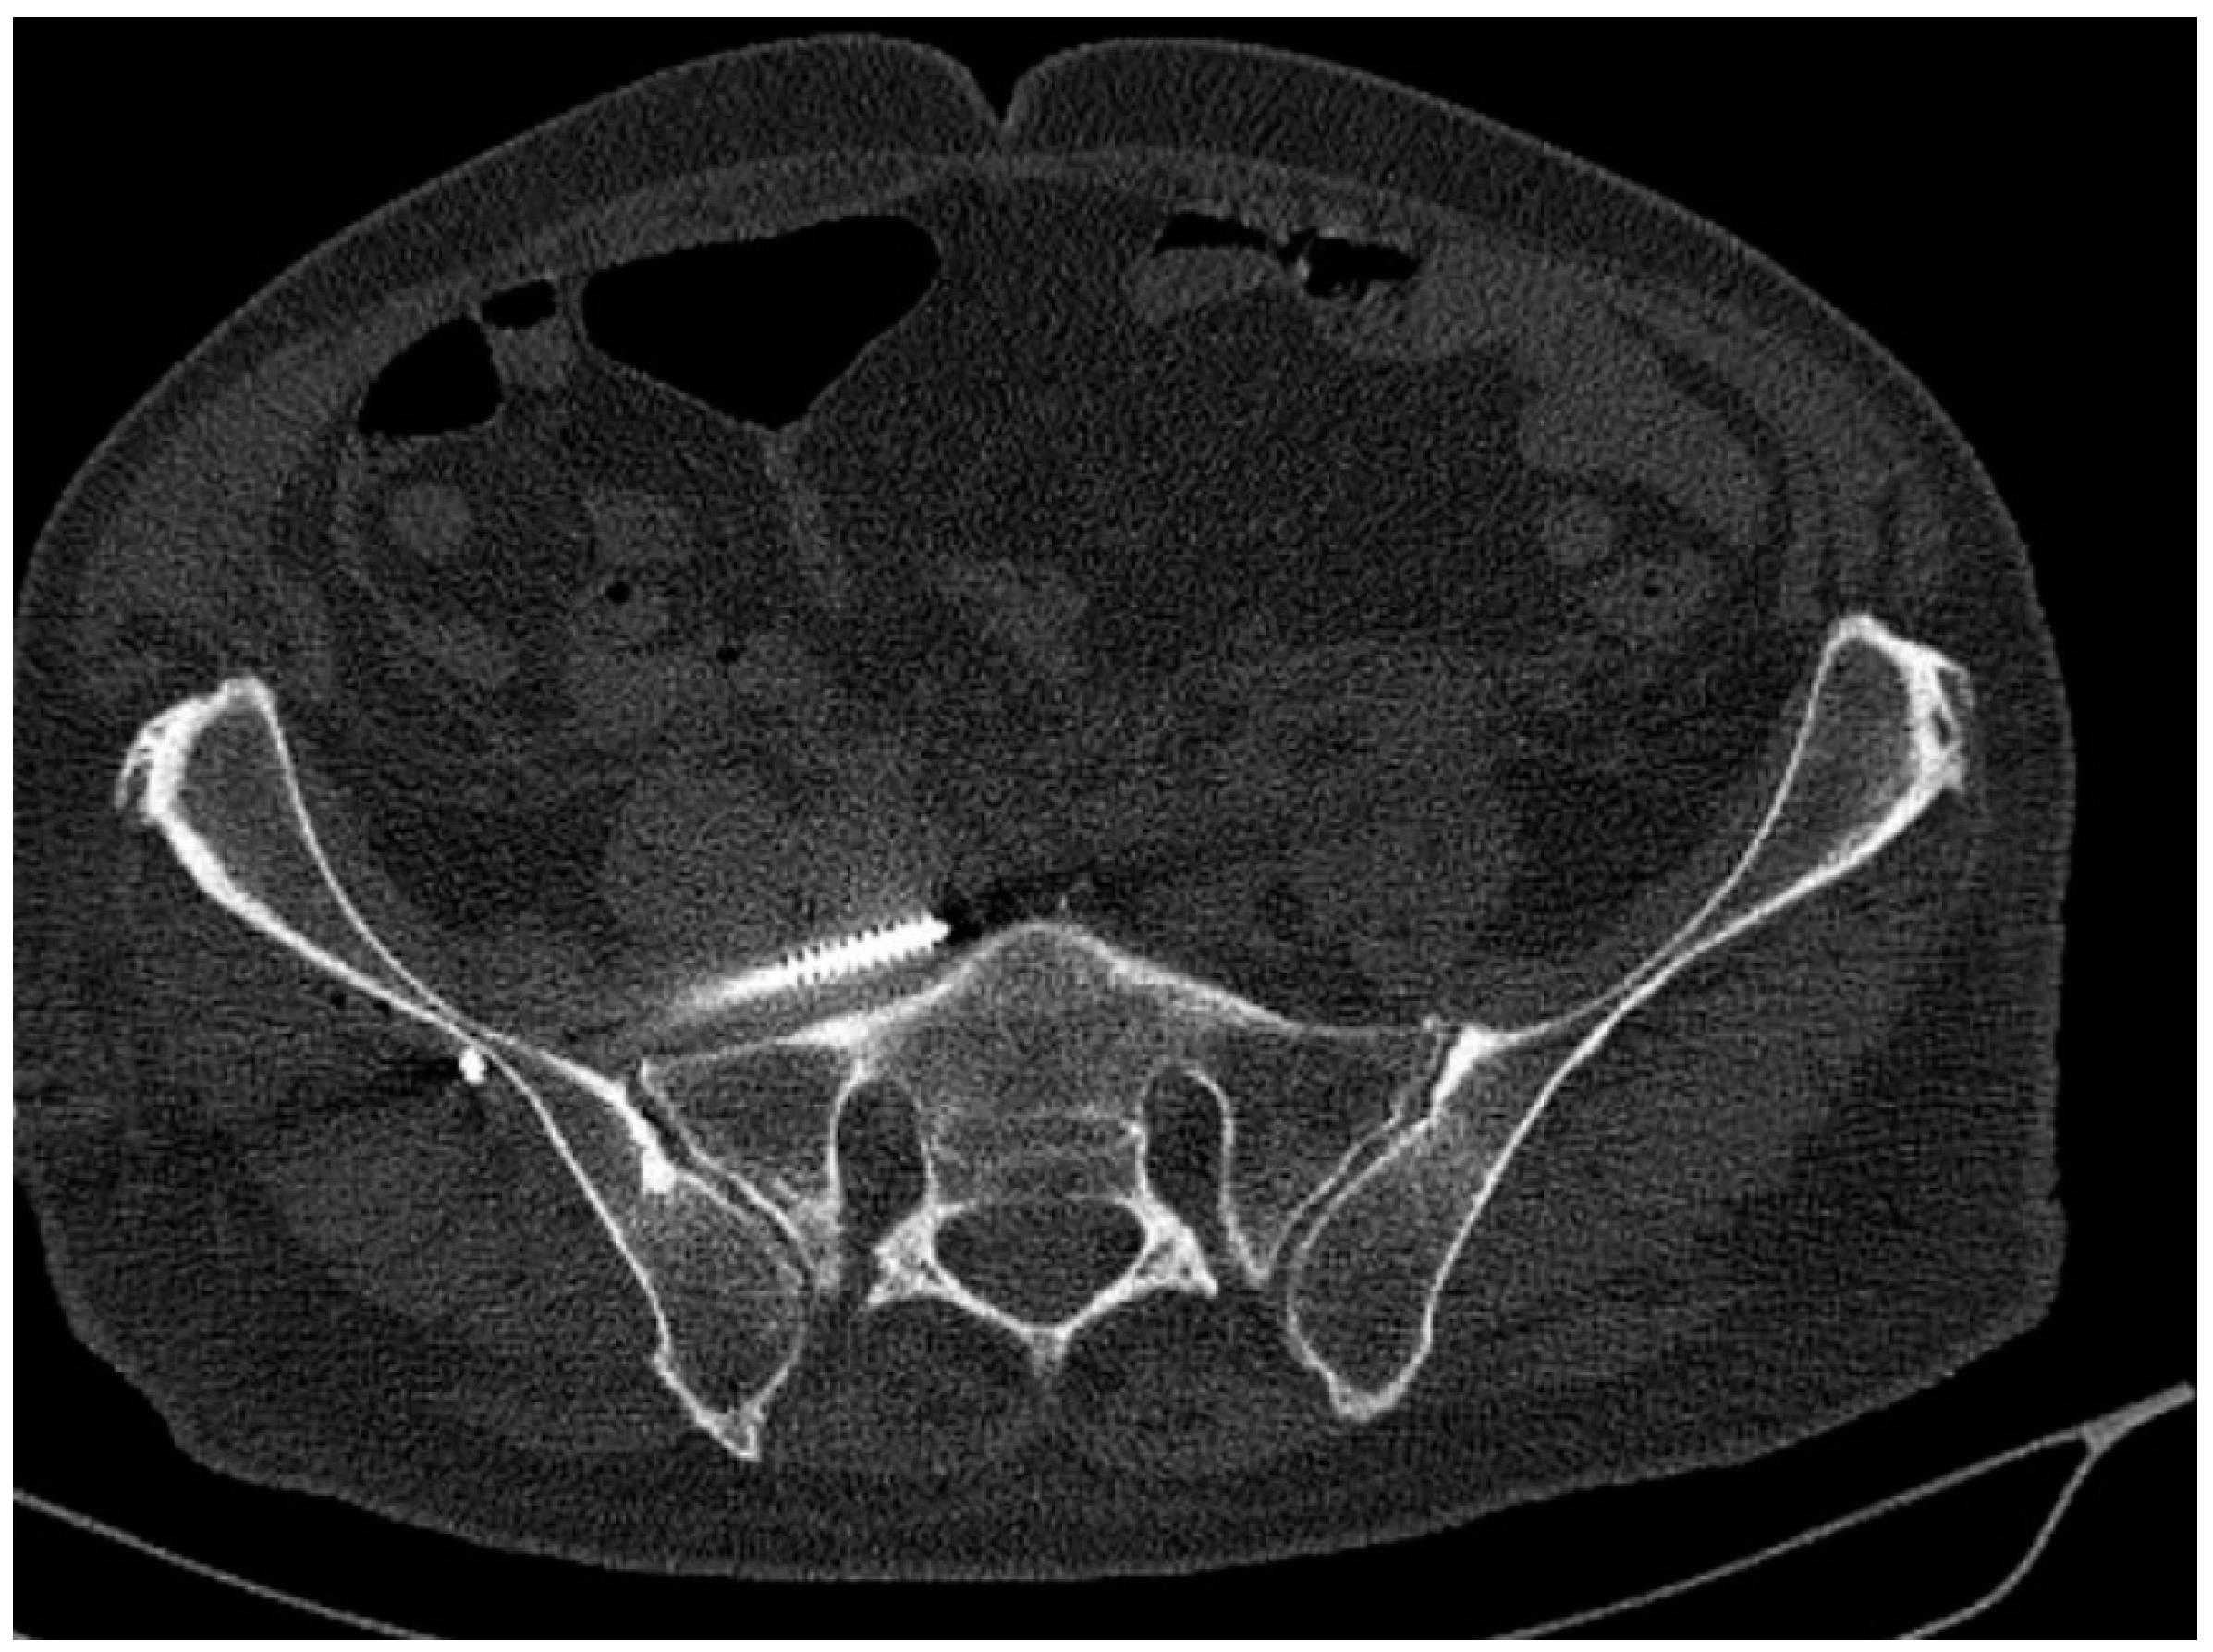

3.2. Number, Localization, and Correct Position of Fixation Screws